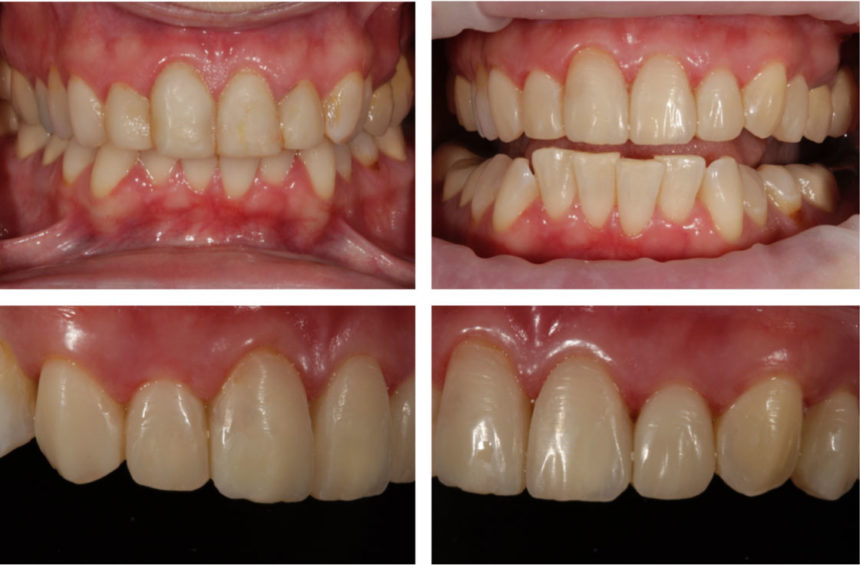

Αποφοίτησε από την Οδοντιατρική Σχολή του Πανεπιστημίου Αθηνών. Έλαβε Μεταπτυχιακό Δίπλωμα Κλινικής Εξειδίκευσης στην Προσθετική και Master of Science στην Οδοντιατρική Σχολή του Ohio State University όπου και εκπόνησε τη Διδακτορική του διατριβή (PhD). Από το 1992 ως το 2000 ήταν Επίκουρος Καθηγητής σε αυτό το Πανεπιστήμιο. To 2002, εξελέγη Επίκουρος Καθηγητής στην Οδοντιατρική Σχολή του Πανεπιστημίου Αθηνών. Από το 2016 είναι Αναπληρωτής Καθηγητής και υπεύθυνος του Μεταπτυχιακού Προγράμματος Επανορθωτικής Οδοντιατρικής. Έχει πραγματοποιήσει πολλές παρουσιάσεις σε Ελληνικά και διεθνή επιστημονικά συνέδρια και έχει πολυάριθμες δημοσιεύσεις. Διατηρεί στην Αθήνα ιδιωτικό ιατρείο με έμφαση στην Αισθητική Οδοντιατρική, Προσθετική και Εμφυτευματολογία.

- Αποκατάσταση κοπτικής γωνίας, κλείσιμο διαστήματος, αλλαγή σχήματος, και όψη σύνθετης ρητίνης. Ανάλυση των μυστικών της επιτυχίας

Όψη σύνθετης ρητίνης

Παρότι θα υπάρχει το απαιτούμενο θεωρητικό μέρος, η έμφαση θα δοθεί στην Βήμα Βήμα πρακτική εξάσκηση από τους συμμετέχοντες σε όλα τα κλινικά στάδια αποκατάστασης πολύπλοκων προβλημάτων προσθίων και οπισθίων δοντιών με σύνθετη ρητίνη.